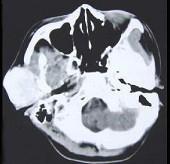

问题 女性,19岁,右侧面颊部肿胀1年,CT检查如图所示,请选择最佳答案()

选项 A.右颊部神经纤维瘤 B.右颊部血管瘤 C.右颊部脂肪瘤 D.右颊部横纹肌肉瘤 E.右颊部血肿

答案 B